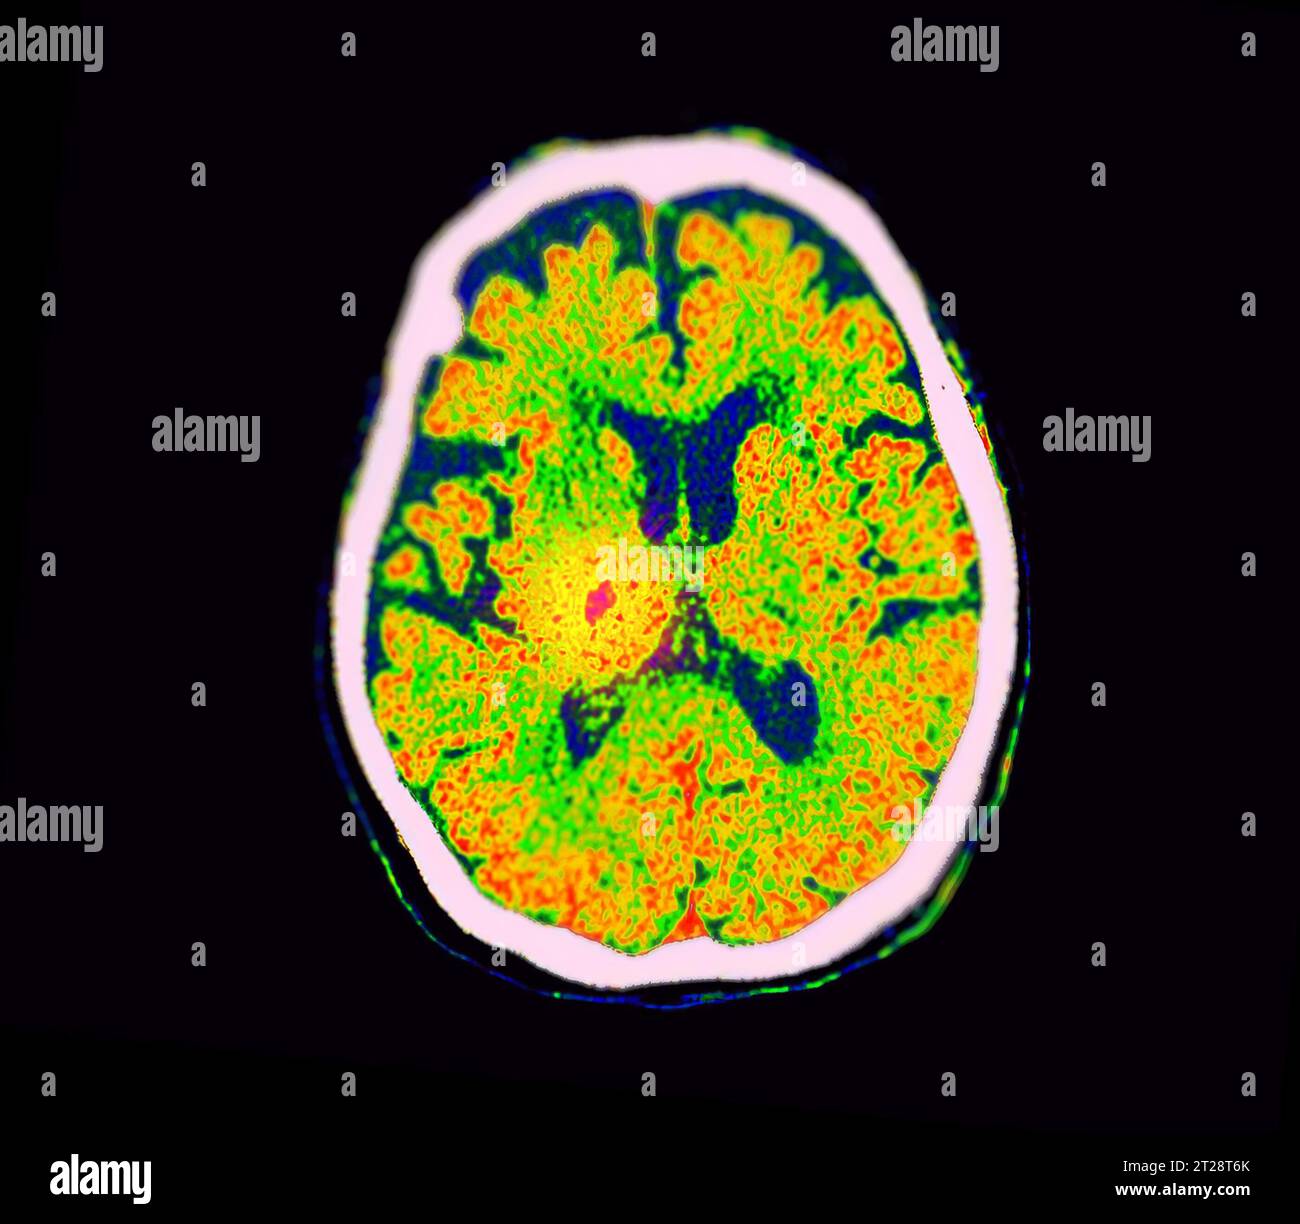

From www.alamy.com

CT Brain Perfusion or CT scan image of the brain axial view showing How Do I Know If I Need A Brain Scan Brain damage, a stroke or Learning that you need to undergo a magnetic resonance imaging (mri) test can be intimidating. a brain mri scan may be prescribed to diagnose a wide range of medical conditions, such as brain injury,. A brain ct scan can also identify fluid, swelling, large tumors, or a large stroke. a brain ct scan. How Do I Know If I Need A Brain Scan.